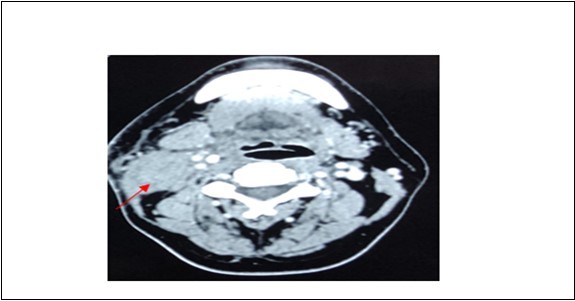

A 42-year-old gentleman, ex-smoker with underlying diabetes mellitus came to our clinic for right neck swelling for about 10 months. The swelling was gradually increasing in size and was giving occasional pain to the patient. But, there were no obstructive symptoms nor a history of prior exposure to radiation. Upon examination, there was a 2x2cm firm, fixed and non-tender swelling palpable at level II of right neck, with no skin changes seen. The facial nerve was intact and the oral cavity was clear. Proceed with flexible scope, there was no mass seen, and laryngeal structures were normal. Fine needle aspiration revealed normal salivary gland elements. A contrasted-CT scan reported a deep lobe parotid gland mass with non-opacification of the right internal jugular vein which could be from compression or thrombosis. [Figure 3] A wedge biopsy was performed subsequently which reported as squamous cell carcinoma, moderately-differentiated. [Figure 4, Figure 5 & Figure 6] Given the malignancy reported, a right total parotidectomy with right selective neck dissection was performed. Post-operatively, the patient developed House-Brackmann grade II facial nerve palsy. Histopathology showed evidence of squamous cell carcinoma with no involvement of adjacent nodes. A final diagnosis of T3N0M0 squamous cell carcinoma of the parotid gland was established. The patient was then referred to the oncology team for chemoradiation. Currently, the patient has completed adjuvant radiotherapy with no signs of recurrence observed so far at six months follow-up.

Figure 3.Contrasted CT neck showing mass at deep lobe of right parotid gland